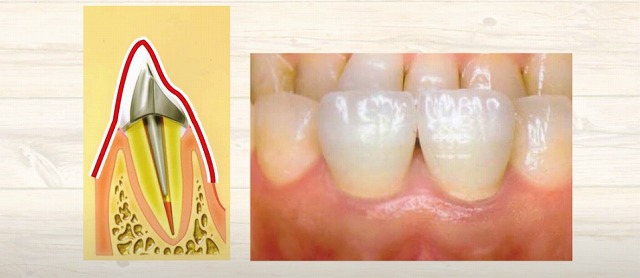

歯はこのように

手鏡等で見ると見えますが、

見えているのは実は

歯の頭だけが見えています。

そして

その下には長い歯の根っこがあって

硬い骨で覆われています。

さらに

薄い歯茎が骨の上に乗っているんですね。

このように

歯の頭があって歯の根っこがあります。

中に

神経や血管があるわけです。

歯の神経の治療をするにあたって、

この歯の頭が邪魔になります。

ですので、

頭をスパーンて

削って落としたりするんですね。

そうすると

歯の神経の入り口つまりトンネルのような状態の筒の入り口が見えてきます。

そこから針みたいなもので、

この穴から入れて中を

ゴソゴソと掃除されたことがあるかもしれません。

断面で見ていきますと、

骨の中に根っこが植わっており中が空洞になります。

空洞になっていますといろいろなものが

入ってきたりしますので、

入ってこないように根っこの中にお薬を入れます

そして被せをしようとしますが安定しません。

ですのでこのようなこのような杭みたいなものをつくり

この杭を穴の中に差し込みます

そうすると、この頭部分が出てきますから

これを土台にして帽子を被せる

というような治療を受けられています。